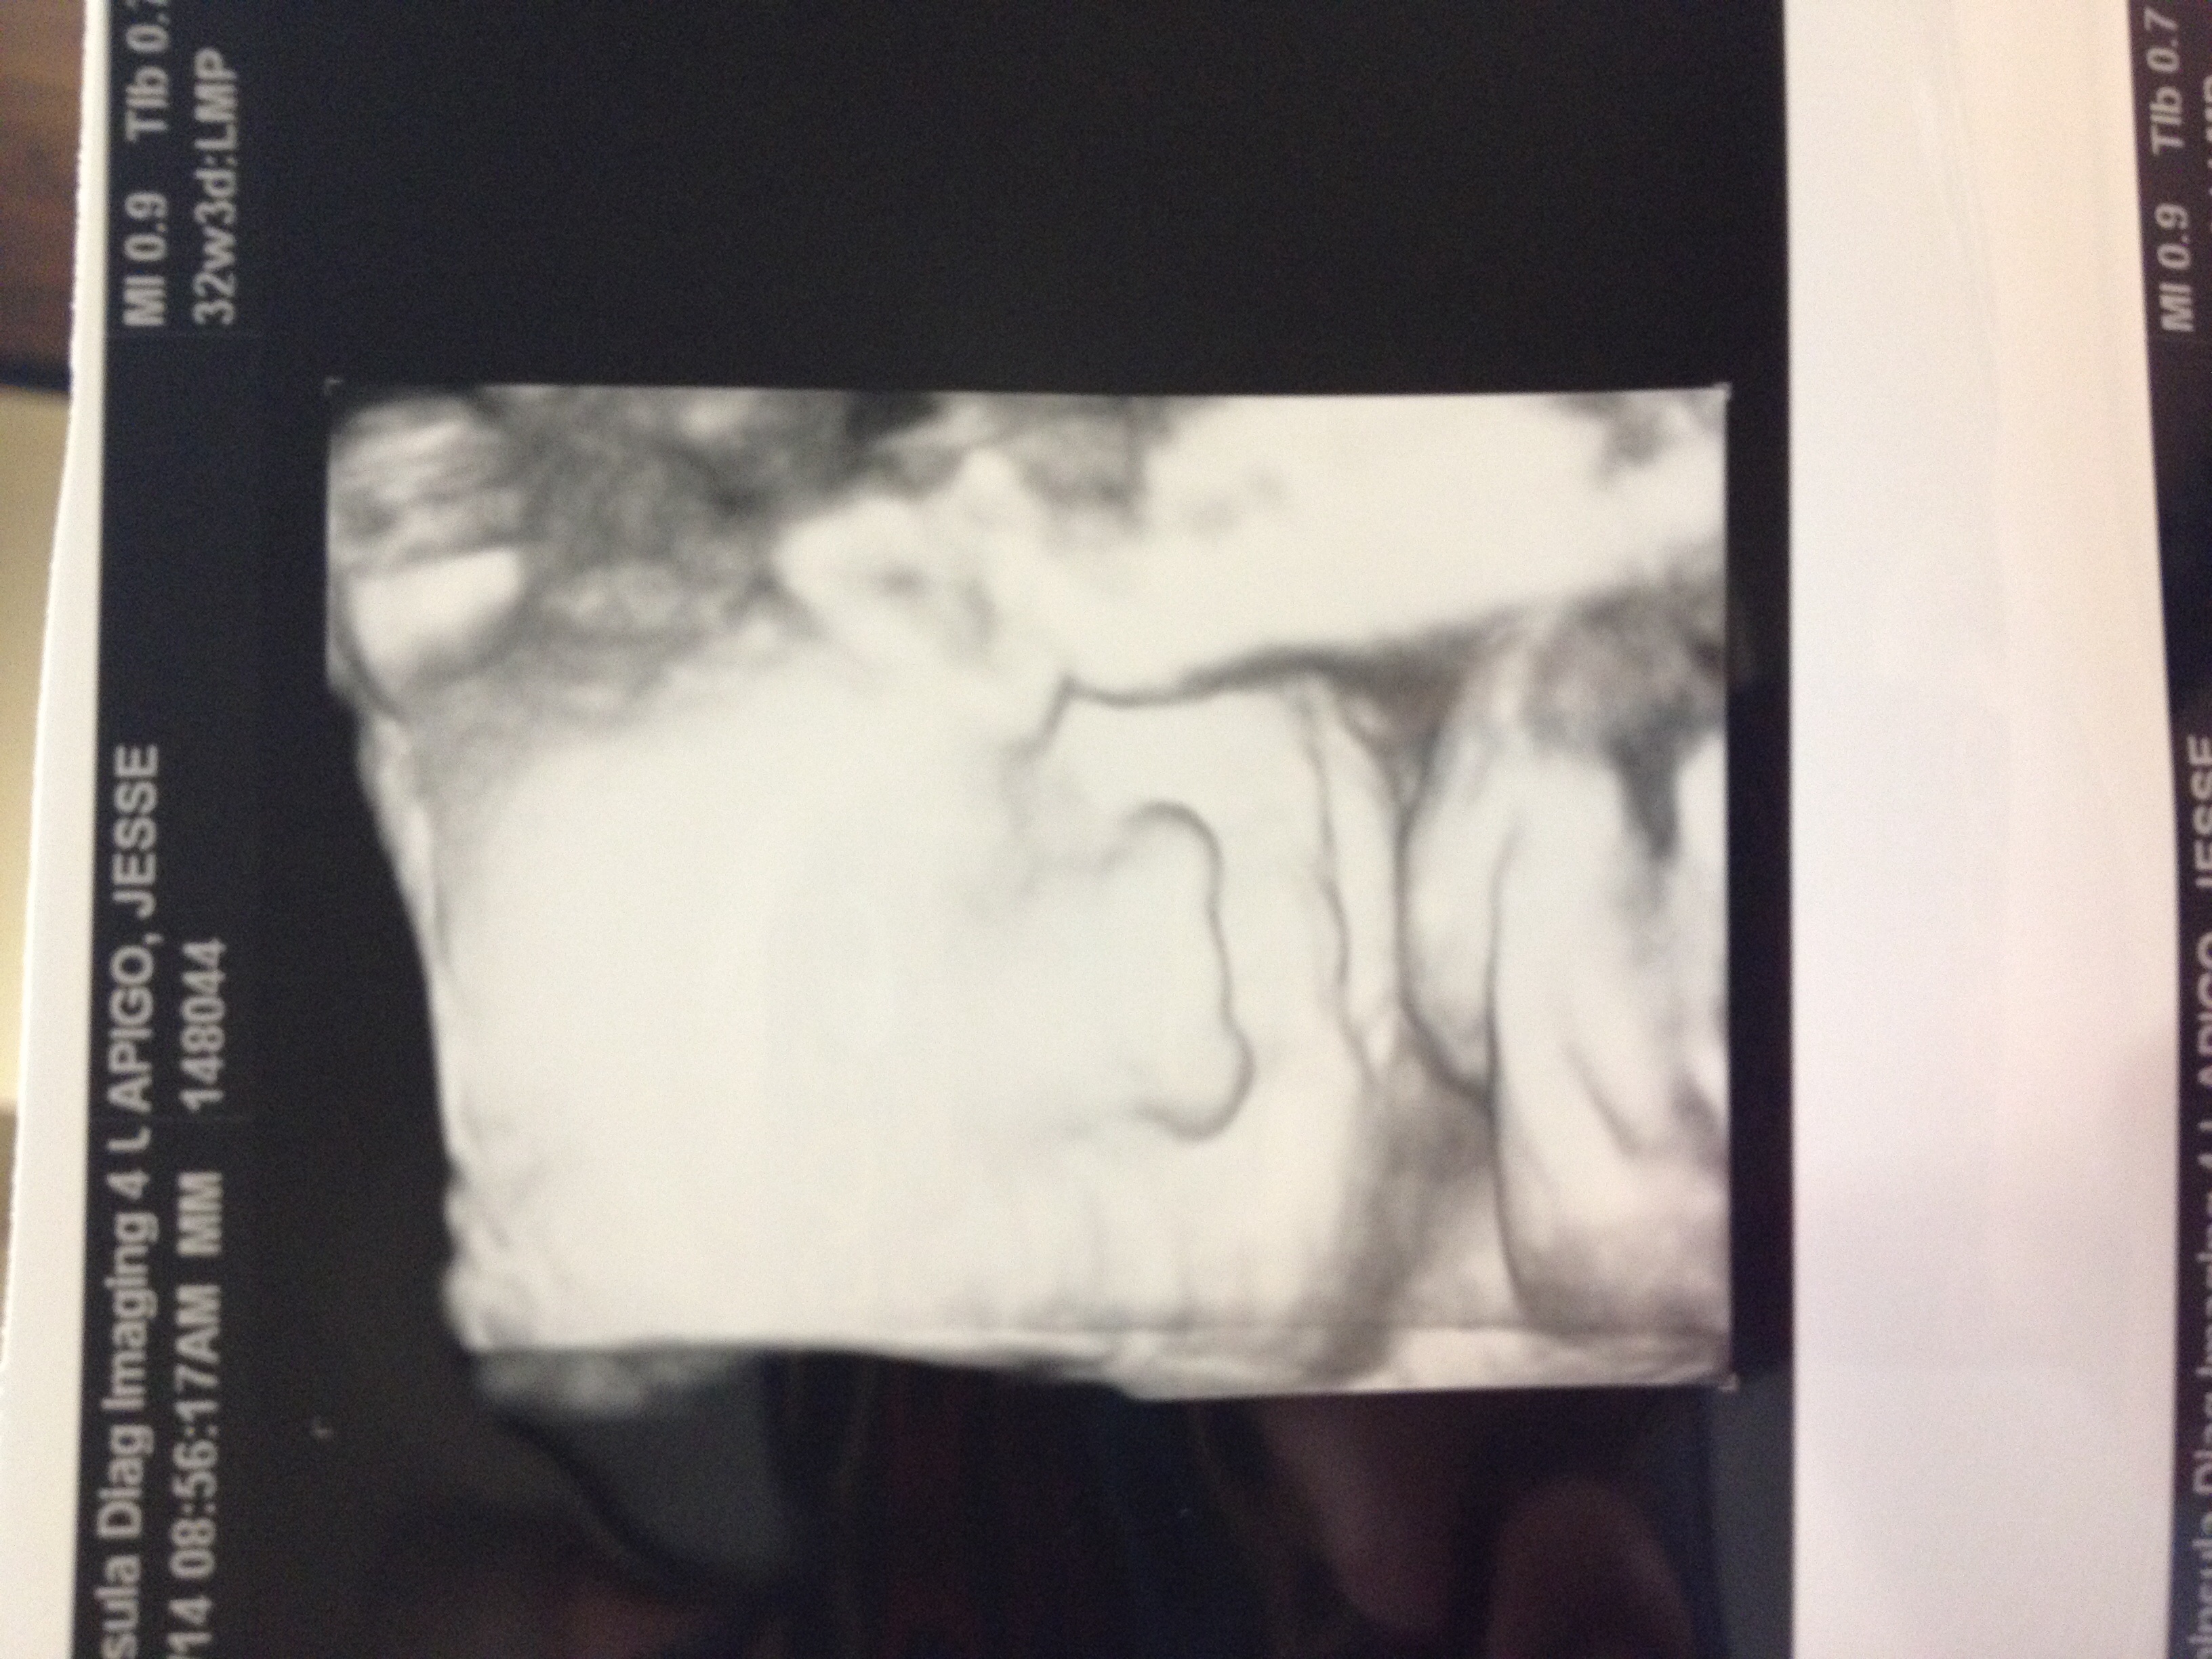

Had a 32 week ultrasound today to check the distance of my placenta to my cervix because it was too close at my 20 week scan. But, thank goodness, as my uterus stretched, my placenta moved up so I'm safe from a scheduled c-section! Woohoo! Also, everything else with baby looked good. He's head down, which means I've been rubbing and talking to his BUTT for the past couple weeks. Best part was the tech got us a couple 3D pics which we didn't expect. He definitely has daddy's flat bridge nose. him.